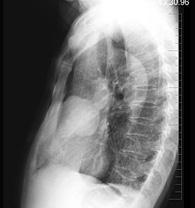

问题 女性,57岁,因胸痛,咳嗽一月就诊,不发热,咳白色痰,无痰中带血,X线检查见图,最可能的诊断是 ( )

选项 A、右肺肿瘤 B、间质性肺疾病 C、右肺炎症 D、纵隔肿瘤 E、右侧肺不张

答案 A